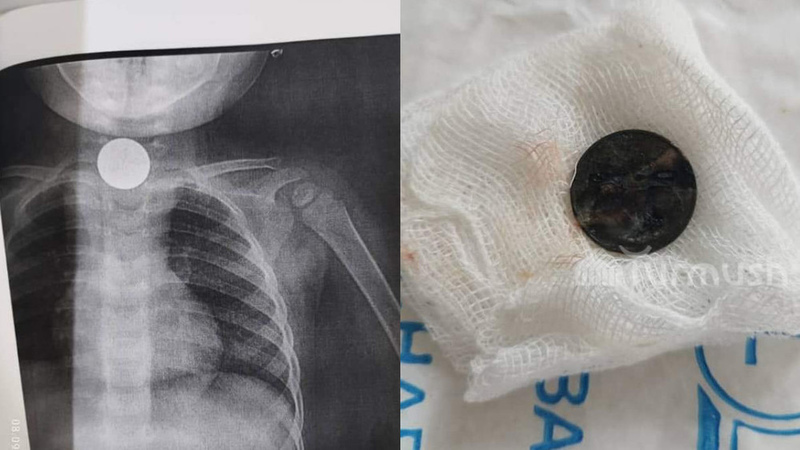

AKIPRESS.COM - A complex operation was performed in the Osh interregional children's clinic on a child who had swallowed a foreign object...